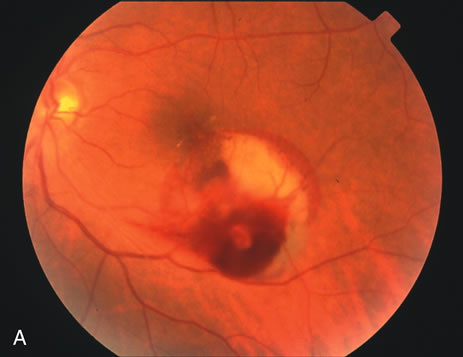

Retinal arterial macroaneurysms often produce retinal edema, circinate hard exudates, and hemorrhage (Fig. 3) into multiple layers of the retina: beneath the retinal pigment epithelium, beneath the retina, within the retina, beneath the internal limiting membrane, between the retina and the posterior hyaloid, and within the vitreous cavity. When the macroaneurysm is obscured by overlying blood, its diagnosis can be challenging.

Fig. 3. A. Color fundus photograph of a macroaneurysm along the inferotemporal arcade with surrounding intraretinal and subretinal hemorrhage. There is retinal edema, hard exudates, and thin subretinal hemorrhage extending into the macula. B. Midphase fluorescein angiography reveals hemorrhage that extends just into the foveal avascular zone, threatening foveal vision. C. Late-phase angiogram reveals staining of the macroaneurysm. D. Color fundus photograph of the same macroaneurysm 6 weeks after laser photocoagulation, demonstrating resolution of the edema and hemorrhage.